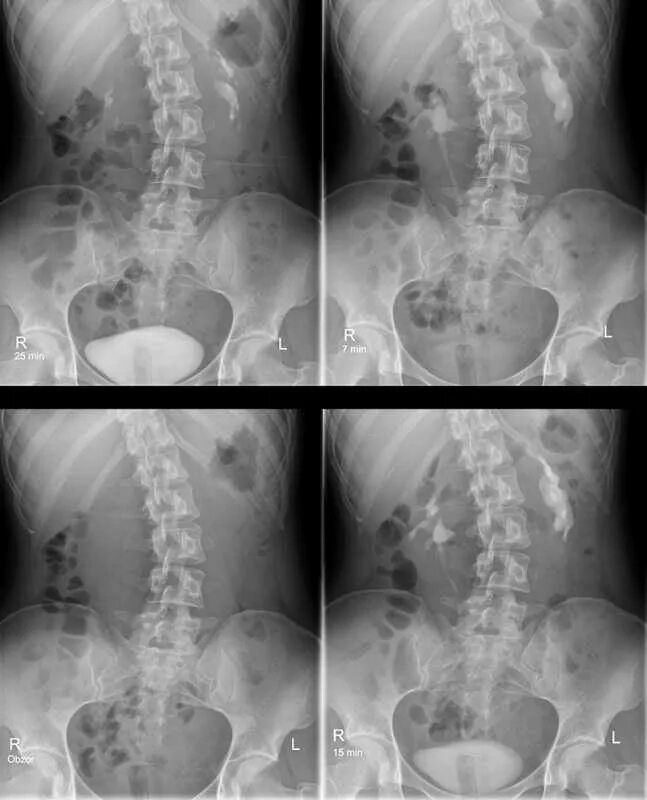

Урография с контрастом